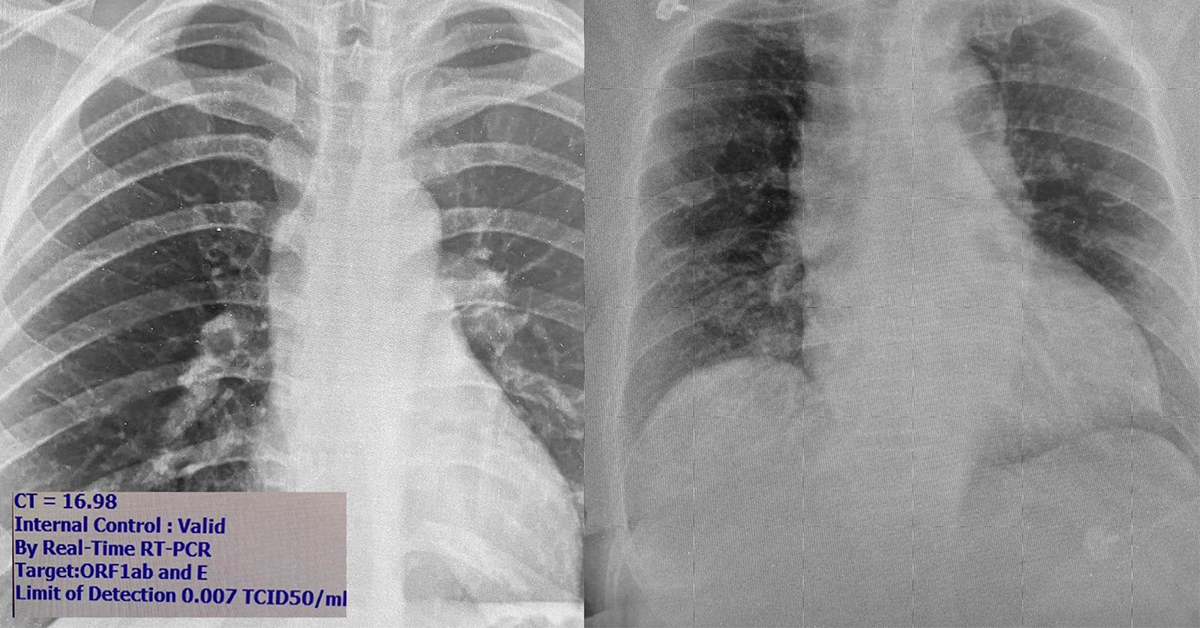

นพ.โอภาสระบุว่า เชื้อสามารถแบ่งตัวได้ดีในจมูกและทางเดินหายใจ คนไม่มีอาการจะมีเชื้อในจมูกเยอะมากพร้อมที่จะแพร่กระจายเป็นวงกว้างเวลาไอ จามหรือพูด ในรูปภาพซ้าย ภาพถ่ายปอดผู้ที่ติดเชื้อที่ไม่มีอาการเลย เดินไปเดินมา ใช้ชีวิตเหมือนคนปกติ แต่เชื้อในจมูกค่า CT (cycle threshold) จากเครื่อง PCR บอกว่ามีปริมาณเชื้อในจมูกสูง มากเมื่อเทียบกับคนไข้ที่เคยเห็นในระลอกแรก ดังนั้นถ้าไม่ได้มาตรวจก็แพร่กระจายเชื้อคนอื่นได้อีกมาก